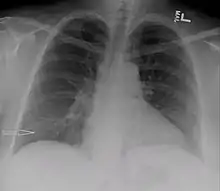

Urinothorax (pl. urinothoraces) is defined as urine in the fluid-filled cavity that surrounds the lungs.[1] It is usually caused by obstructive uropathy. It is mainly diagnosed by analyzing the pleural fluid. Treatment involves treating the underlying condition, which typically results in resolution of the urinothorax. It is an extremely rare cause of pleural effusion.[2]

| Right sided pleural effusion caused by urinothorax | |